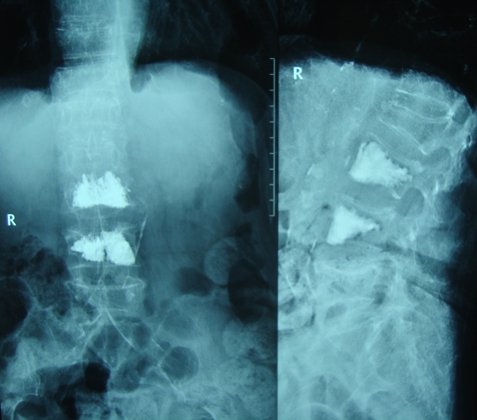

图5.老年骨质疏松患者椎体压缩骨折椎体成形术后